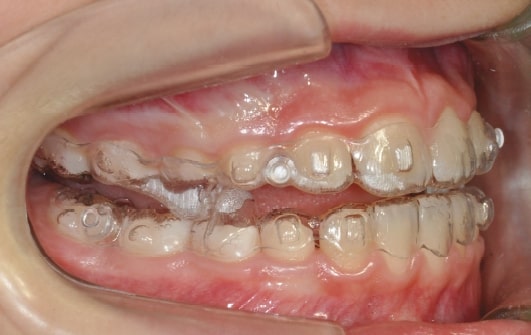

Treatment details

AngelAligner KiD 1 (aligners changed every 10 days)

- Upper frenulum surgery

- Class 1 both sides

- Overjet/Overbite Correction

Treatment progress